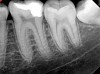

Fig 1. through Fig 3. Root filled with bioceramic sealer cut at different distances from the apex (Fig 1 through Fig 3: 0.5, 1.5, and 3.0 mm). One gutta-percha point is used as a plugger to move the sealer using hydraulic pressure. Note the irregularities are very well filled.

Pre-mixed BC Sealer is the only pure medical-grade bioceramic product available as a sealer for endodontic obturation. It has the same basic chemical composition as the other pre-mixed bioceramic products, but it is less viscous, which makes its consistency ideal for sealing root canals. It is used with a gutta-percha point, which is impregnated on the surface with a nano particle layer of bioceramic. The gutta-percha is used primarily as the delivery device (plugger) (Figure 1 through Figure 3) to allow hydraulic movement of the sealer into the irregularities of the root canal and accessory canals (Figure 4 and Figure 5).